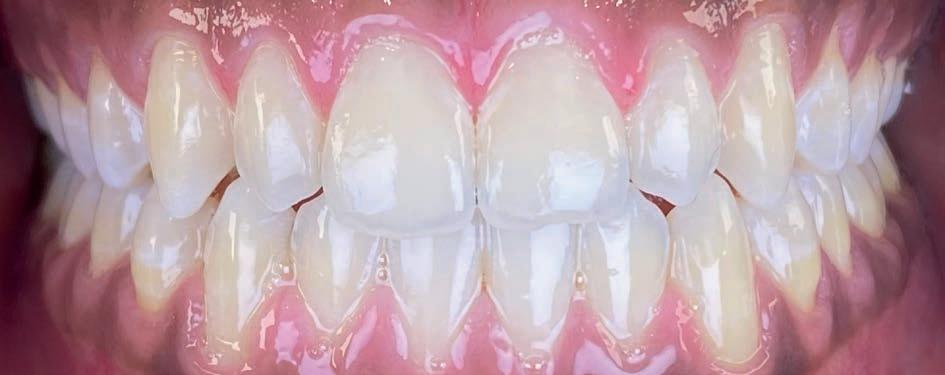

Casus: Jorn

Niet-chirurgische correctie van een Klasse III-relatie

Patiënt: Jorn (18 jaar)

Behandelduur: 15 maanden

Behandeling: Damon Ultima brackets en elastieken

Jorn en zijn vader kwamen via Google bij Clover

Orthodontie terecht, nadat hij elders een chirurgisch behandelvoorstel had gekregen. Als actieve voetballer paste een operatie niet in zijn leven. Hij presenteerde zich met een skeletale Klasse III-relatie, anterieure kruisbeet, negatieve sagittale overbeet en een concaaf profiel.

Behandelstrategie

Er werd gekozen voor een behandeling met Damon Ultima brackets en een strak gepland elastiekprotocol. Vanaf het begin droeg Jorn Klasse III-elastieken om de sagittale discrepantie te corrigeren. Dankzij de precisie en lage frictie van Damon Ultima konden we transversaal én sagittaal corrigeren zonder chirurgische ingreep.

Het eindresultaat bestond uit een stabiele Klasse I-occlusie met een duidelijk verbeterd profiel. Er zijn geen extracties of chirurgische ingrepen uitgevoerd. Voor de retentie werd gekozen voor vaste spalken in combinatie met nachtbeugels, om het bereikte resultaat langdurig te behouden.